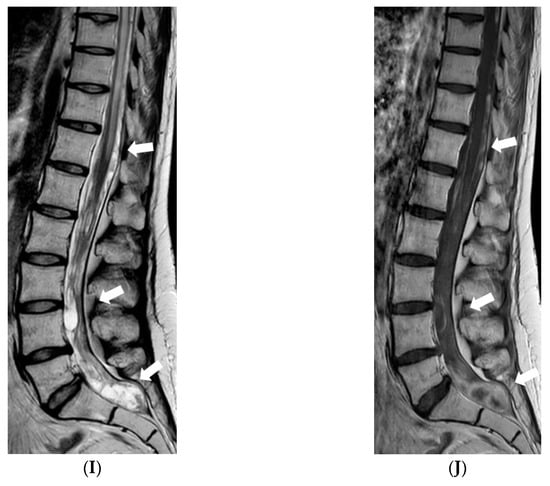

Due to impaired vision, further loss of hearing, and ability to walk, an MRI of the brain and spine was repeated in 2020. MR brain revealed residual changes—cystic leptomeningeal-subpial nodular lesions that were hypointense on T2W/FLAIR, and did not show contrast enhancement in the posterior fossa and along the basal cisterns, surrounding the brainstem, cranial nerves, and cerebellum. Imaging of spinal cord revealed cystic nodular lesions resembling those found in the brain and causing persistent, multisegmental spinal cord compression (Figure 6).

Figure 6.

Follow-up MRI of the brain and spinal cord 9 years after the onset of symptoms (November 2020): (A) Axial T2W/FLAIR, (B,C) and (D) sagittal T1W post-contrast images demonstrate residual non-enhancing cystic lesions in basal cisterns and posterior fossa surrounding brainstem and cerebellum. (D) Sagittal T1W post-contrast image shows diffuse atrophy of the cerebellum. (E,G,I) Sagittal T2W and (F,H,J) T1W post-contrast images of (E,F) cervical, (G,H) thoracic, and (I,J) lumbar spinal cord reveal diffuse intradural extramedullary mixed cystic and solid lesions that show medium contrast enhancement and slight compression of spinal cord at various levels.